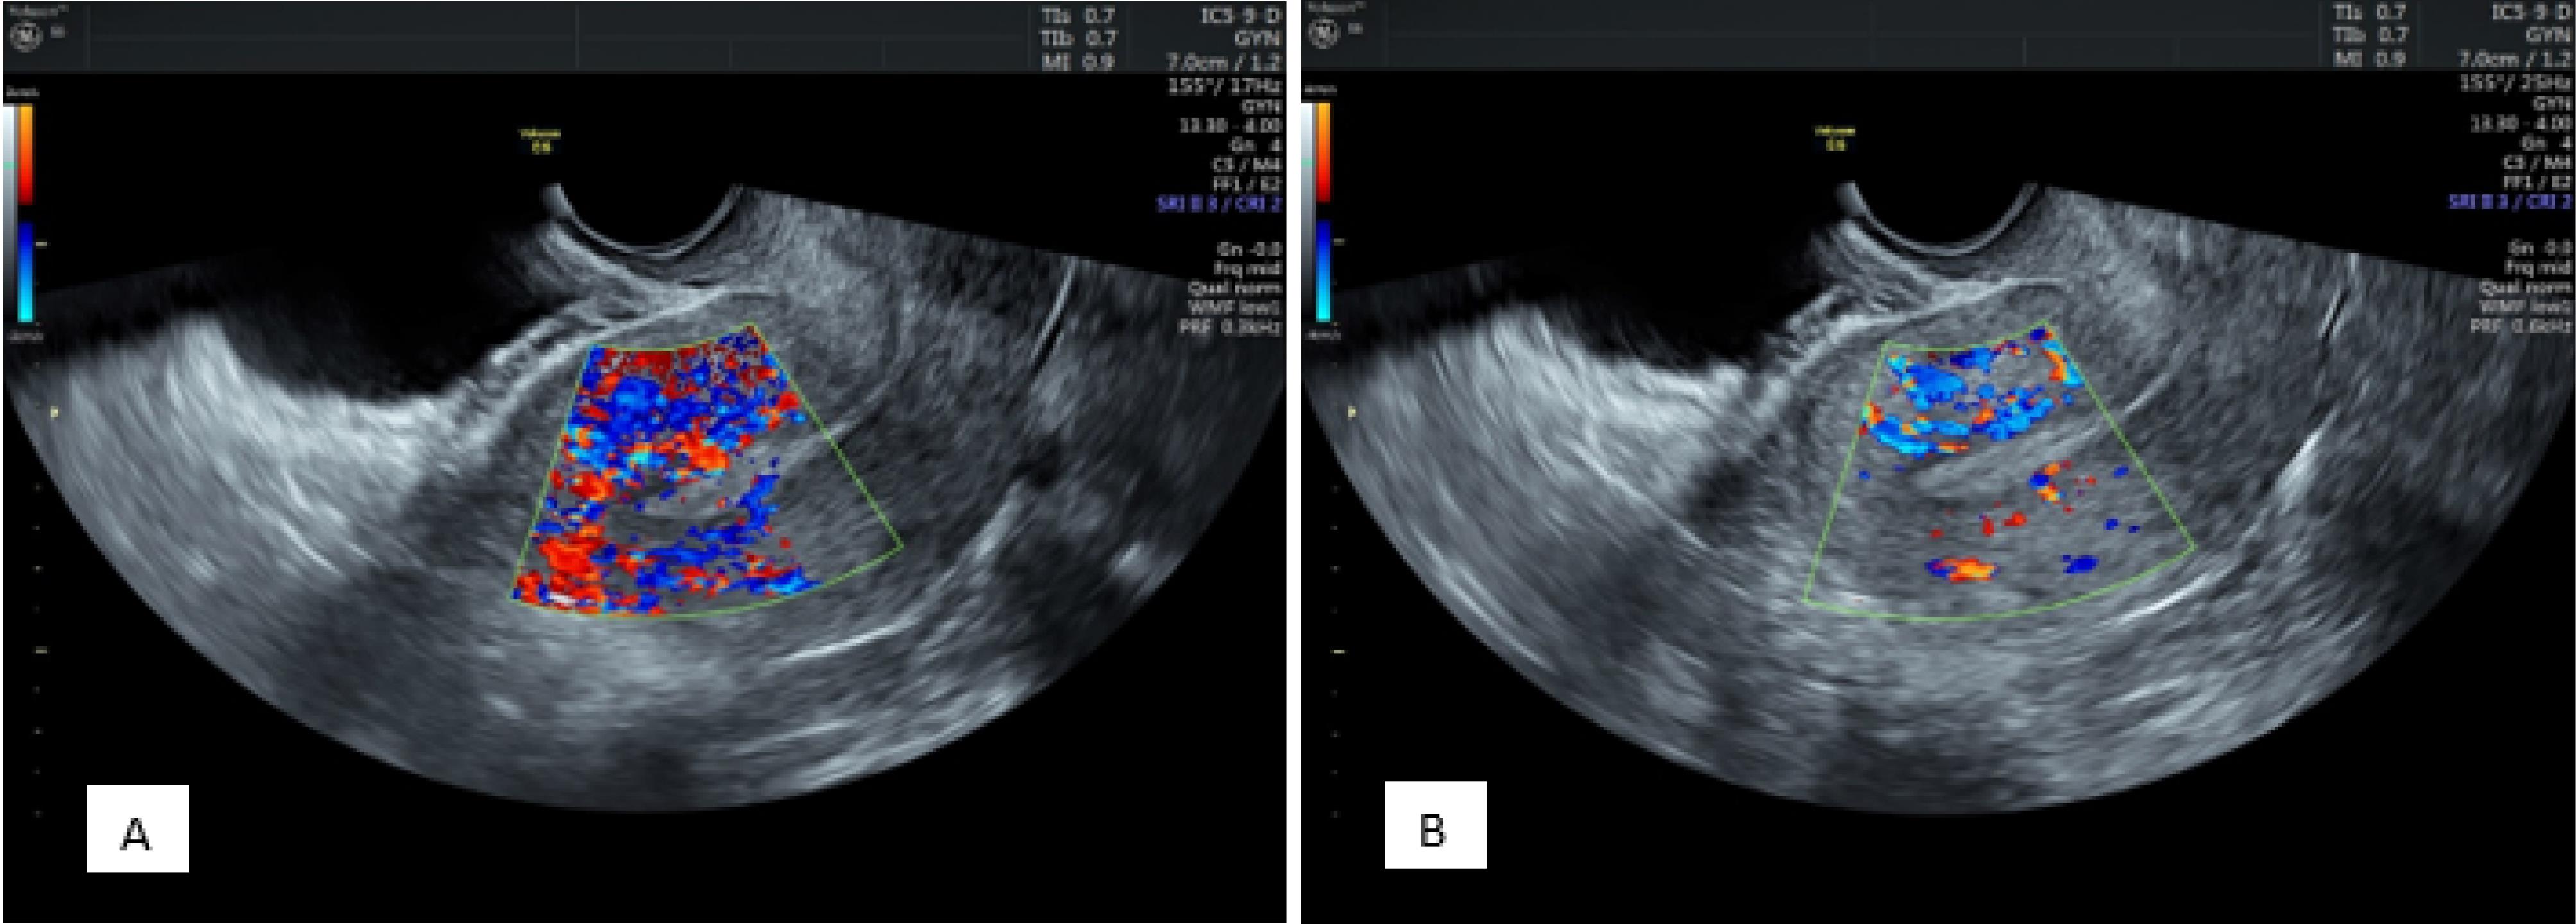

The overall endometrial thickness significantly decreased after progesterone administration (before progesterone administration: 9.66 ± 1.69 mm vs. 8.86 ± 1.76 mm after progesterone administration, P < 0.001). In addition, there were significant changes in endometrial thickness before progesterone administration between the pregnant and nonpregnant groups (10.11 ± 1.97 mm and 9.36 ± 1.39 mm, respectively, P = 0.004). Endometrial thickness was still significantly greater in the pregnant group (9.26 ± 1.94 mm) than in the nonpregnant group (8.59 ± 1.58 mm) after progesterone administration (P = 0.011, Figure 2).

Figure 2.

Endometrial Thickness and View Before (A) and After (B) Progesterone Administration Showing a Decrease in Thickness and Changing From a Clear Three-Layer View Containing a Central Hyperechoic Line Surrounded by Two Hypoechoic Layers to an Endometrium Without Distinguishable Layers

Endometrial Views

Before progesterone administration, 13 patients had an endometrium without layers, 30 had three unclear layers, and 157 had three clear layers. After progesterone administration, the endometrium consisted of 106, 38, and 56 without layers, three unclear layers, and three clear layers, respectively (P < 0.001, Figure 2).

Comparing the appearance of the endometrium before the administration of progesterone in the two groups, in the positive group, 9 were without layers, 14 had three unclear layers, and 58 had three clear layers, and in the negative group, 4 were without layers, 16 had three unclear layers, and 99 had three clear layers (P = 0.056).

Based on the comparison results regarding the appearance of the endometrium after the administration of progesterone in the two groups, in the positive group, 33 were without layers, 9 had three unclear layers, and 39 had three clear layers. In addition, in the negative group, 67 were without layers, 29 had three unclear layers, and 23 had three clear layers (P = 0.002).